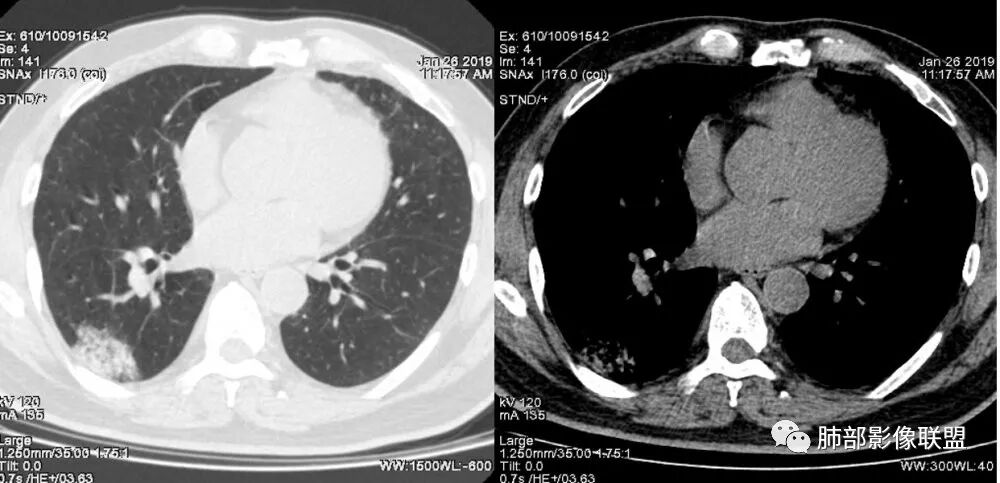

老年女性,咳嗽咳痰病史,右肺下叶大片磨玻璃实变影,胸膜下分布,支气管进入后扩张、僵直,磨玻璃影边界清楚,考虑粘液腺癌。鉴别肺炎。

右肺下叶基底段靠胸膜实变/磨玻璃混杂密度影,边界清楚,内见多发空泡(蜂窝样趋势改变?); 临床:咳嗽咳痰,无发热、胸痛; 考虑腺癌:无发热,感染性病变不首先考虑;部分层面形态类楔形,鉴别肺栓塞

老年人,右肺下叶斑片状阴影,病灶有膨胀性,边缘可见磨玻璃影,其边界清晰,内见僵硬的支气管,部分支气管扩张,首先考虑占位性病变,粘液性腺癌可能。鉴别感染性病变,后者边缘多有收缩性改变或者平直,内部支气管走形自然。

老年女性,右下肺实变影,糊墙,外朝内发展,病灶里有小叶内间质增厚,周围边界清楚了GGO,支气管扩张明显,考虑粘液癌;不符合点,支气管扩张太厉害了,鉴别淋巴瘤。

患者中年女性,咳嗽咳痰就诊。胸部CT:右肺下叶后基底段片状实变影,由胸膜向内发展呈扇形,病灶里有小叶内间质增厚、蜂窝状影,周围边界清楚GGO,内可见扩张支气管,淋巴结无明显肿大。综合符合粘液腺癌。

老年女性,咳嗽、咳痰。右肺下叶沿胸膜下大片状高密度影,外周磨玻璃影,边界较清,小空泡,蜂窝征及支气管充气征,叶间裂串珠征,考虑:肺炎型肺癌,鉴别:肺克,链球菌,NTM等感染。

右肺下叶胸膜下大片状MGGO,其内结构紊乱,可见空泡征,病灶内近端支气管扩张,远端闭塞,形态不规则,边界部分清楚,部分似清非清,考虑粘液腺癌,鉴别淋巴瘤

2.病灶示中央实变区,周围GGO,可见明显小叶间隔增厚,GGO边界清楚,应当考虑到恶性病变的可能性。肺炎因炎性水肿及渗出,影像上边界常模糊不清,注意早期粘液腺癌可出现似清非清的边界。粘液腺癌因粘液成份较多,密度一般偏低,纵隔窗病灶常会消隐或范围会明显缩小,这不同于炎性实变。

3.病灶内支气管走形略显僵直,侧支少(粘液阻塞),也符合肺腺癌的枯树枝征。而大叶性肺炎的支气管是管壁光整、通畅、自然,结核的支气管常常壁增厚,甚至狭窄后扩张;